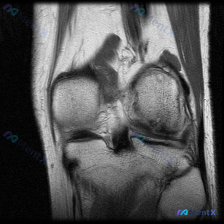

今天整理了一个很有代表性的读片病例,临床和影像存在核心矛盾,分享一下分析思路。 病例影像基础信息 这是一份膝关节冠状位T1加权MRI单张图像,影像科对图像的系统评估如下: 1. 骨骼:股骨远端、胫骨近端结构完整,骨皮质连续,骨髓信号正常,无骨赘 2. 半月板:内、外侧半月板形态、信号均正常,无异常信...